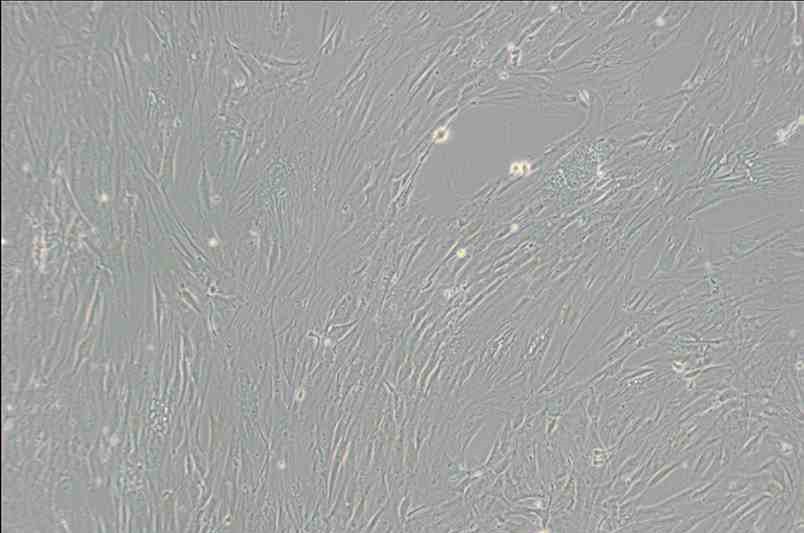

CCD-1095Sk人乳腺浸潤性導管癌旁皮膚細胞

細胞簡稱 :C C D -1095Sk

細胞形態 :成纖維細胞樣

生長特性 :貼壁細胞

C C D -1095Sk細胞從左乳房的活體組織切片的正常皮膚建立,病人患有乳腺浸潤性導管癌并患有乳頭濕疹樣癌本病。這一代次的細胞已經過兩次數目倍增,約可再進行10次數目倍增。